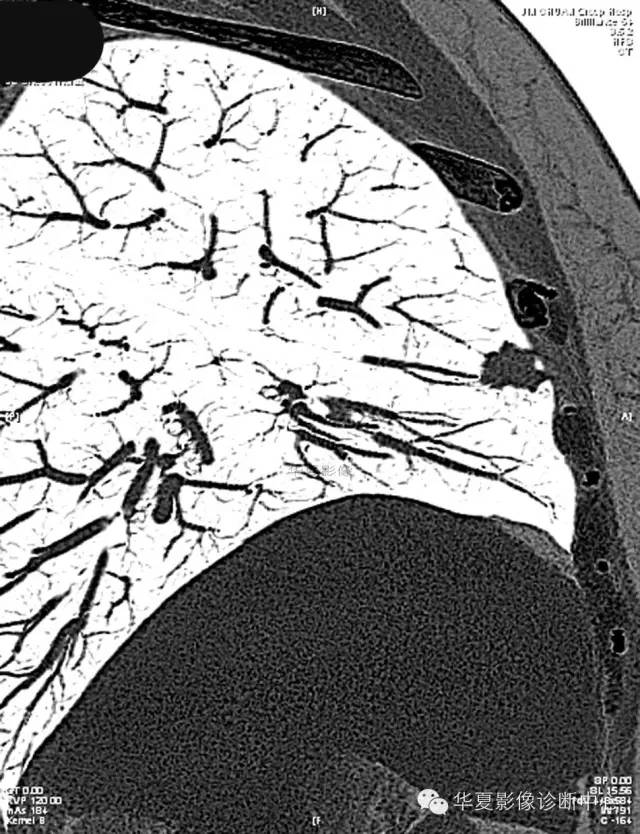

女,56岁,其父因肺癌去世,自觉胸部疼痛不适来诊要求拍胸片。

检查结论:

(右)肺中分化鳞状细胞癌。浸及胸膜。支气管残端切净。淋巴结未见癌转移(0/10)。